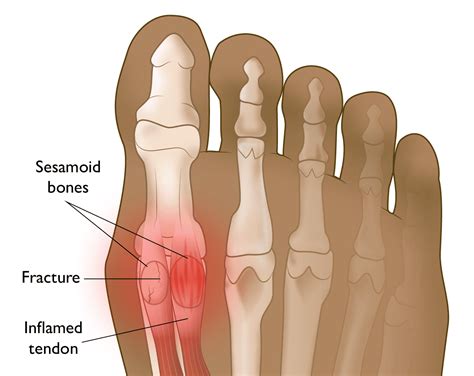

• Sesamoiditis: This is an inflammation of the sesamoid bones and the surrounding tendons. It is often caused by overuse, high-impact activities, or improper footwear.

• Sesamoid Fracture: A fracture of the sesamoid bones can occur due to a sudden impact or repetitive stress. This condition is often seen in athletes and dancers.

The sesamoid bones are small, round bones embedded within tendons. In the foot, there are two sesamoid bones located beneath the head of the first metatarsal bone, which is the long bone connected to the big toe. These bones are named the medial and lateral sesamoid bones, and they act as pulleys for the tendons that control the big toe.